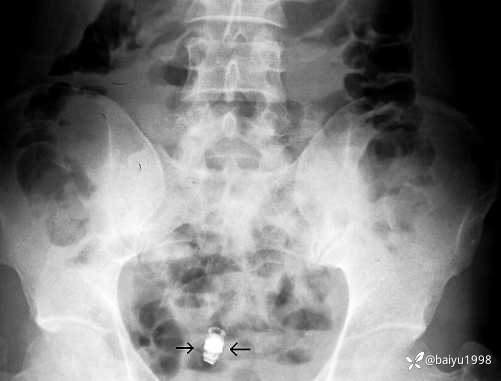

这篇个案报道是在2007年发表在Endoscopy杂志,中年男性因为腹痛、贫血,胃肠镜检查和腹部CT均阴性后,在外院进行了胶囊内镜检查,在胶囊内镜检查后多日发现未能排出体外,腹部X线证实胶囊滞留,入我院行小肠镜试图取出胶囊内镜失败,随后患者的腹部梗阻症状加重,最终接受了外科手术治疗,证实了小肠克罗恩病的诊断。

图1、胶囊内镜滞留在体内